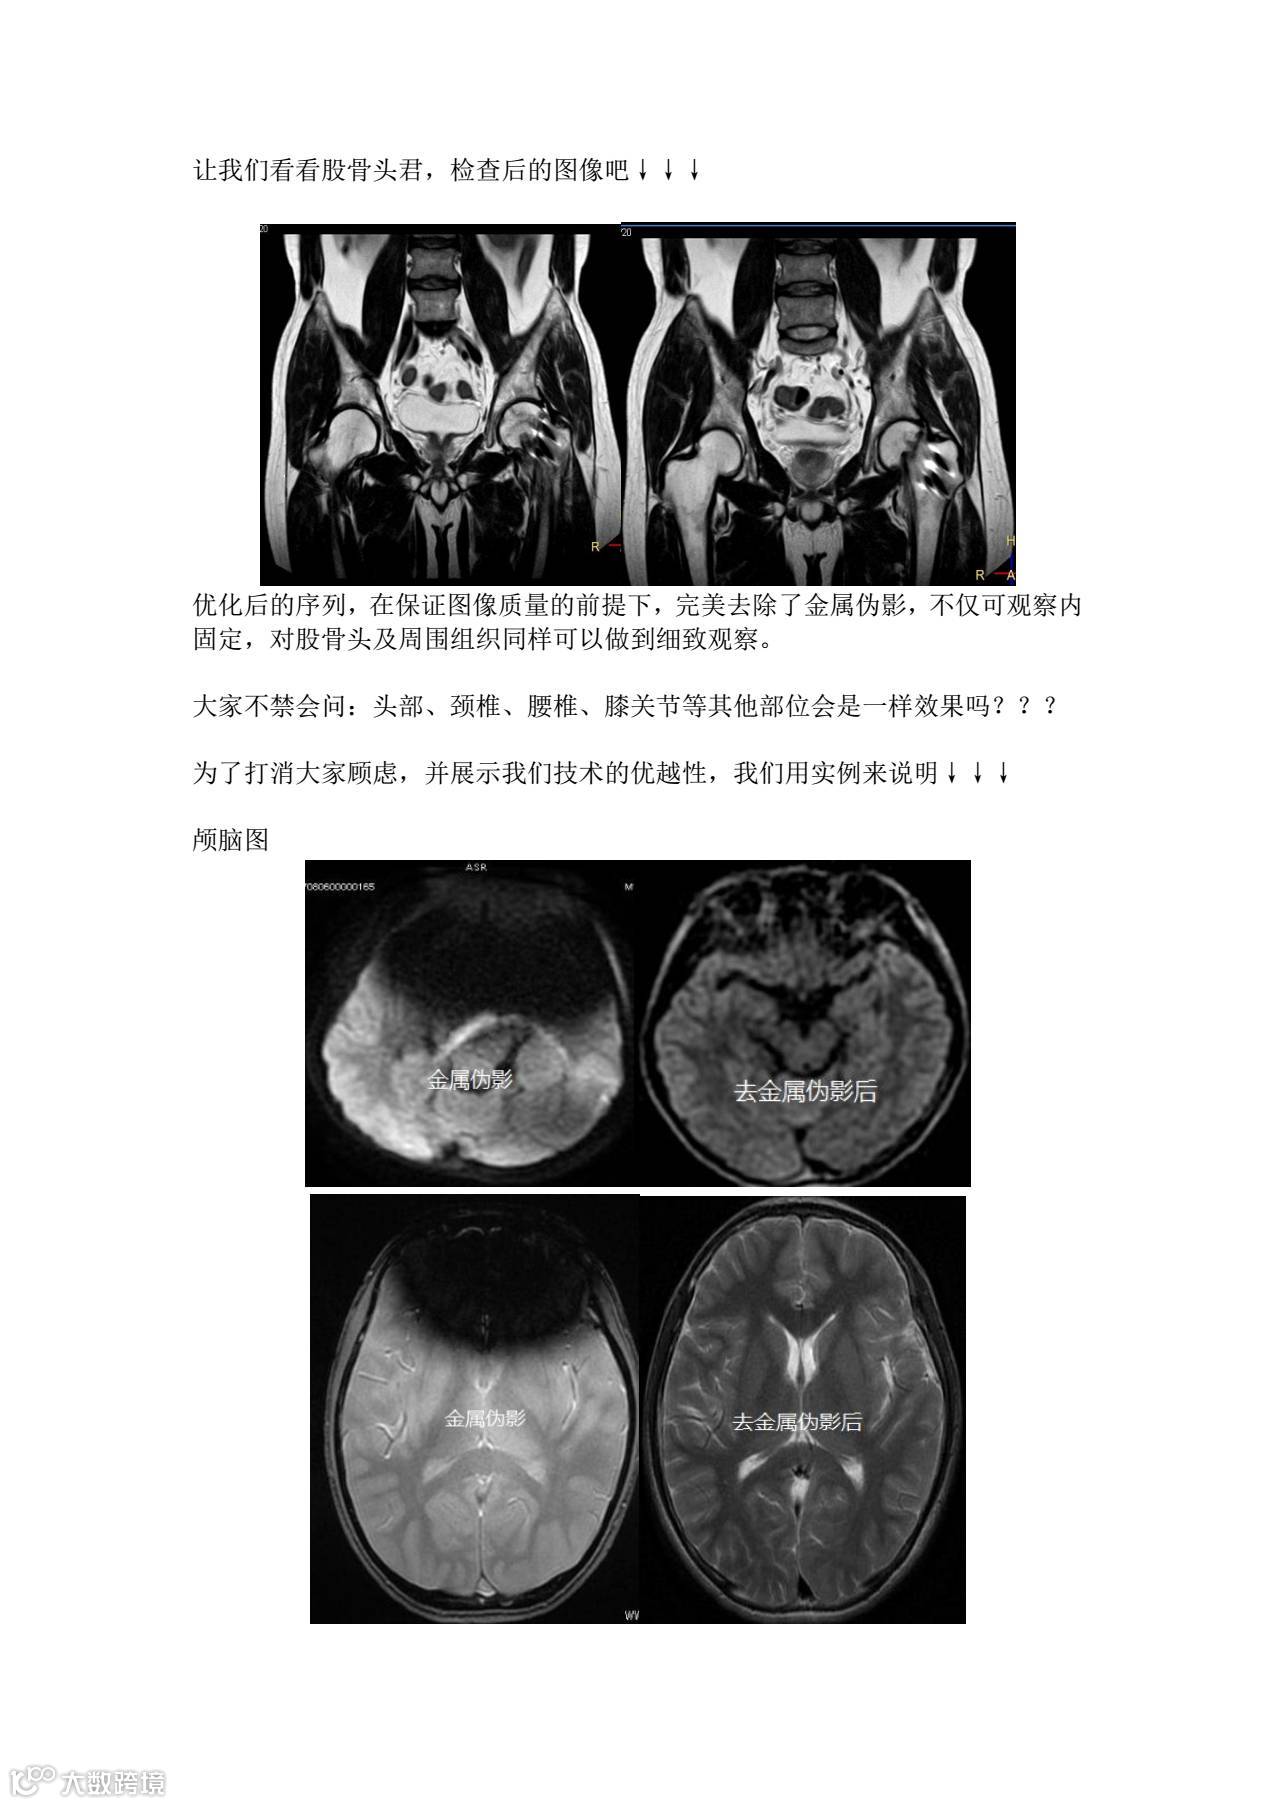

导读:【新技术】核磁共振去金属伪影